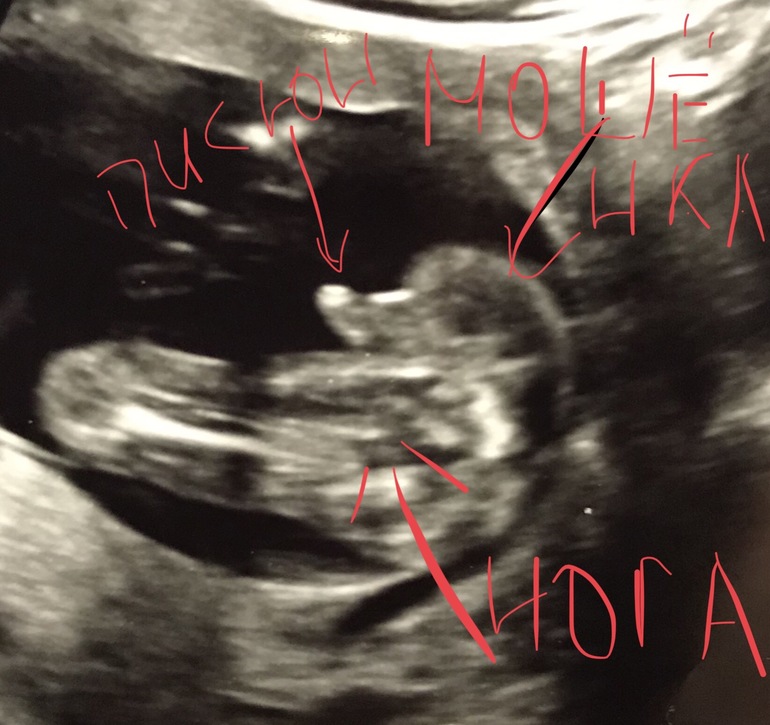

И всё таки - это сыночек!

УЗИ, КТГ, доплерДевочки, кто сделал анализ крови на определение пола малыша, и думаете, что это 100%, могу сказать - он ошибается. Может я и попала в 1%, но в 11 недель мне анализ крови показал 99% женский пол, в 12 недель 1 скрининг - «больше похоже на девочку», в 14,5 недель узи - предположительно женский плод, в 16 и 4 - мальчик. Мне на прошлый пост - 5 человек написали, что последнее узи врет, а кровь - это точно. Так вот, была сегодня на внеплановом (тянуло 2 дня живот) узи в жк (аппаратуры сами понимаете, не очень, так врач сразу же сказала, 100% мальчик!!!